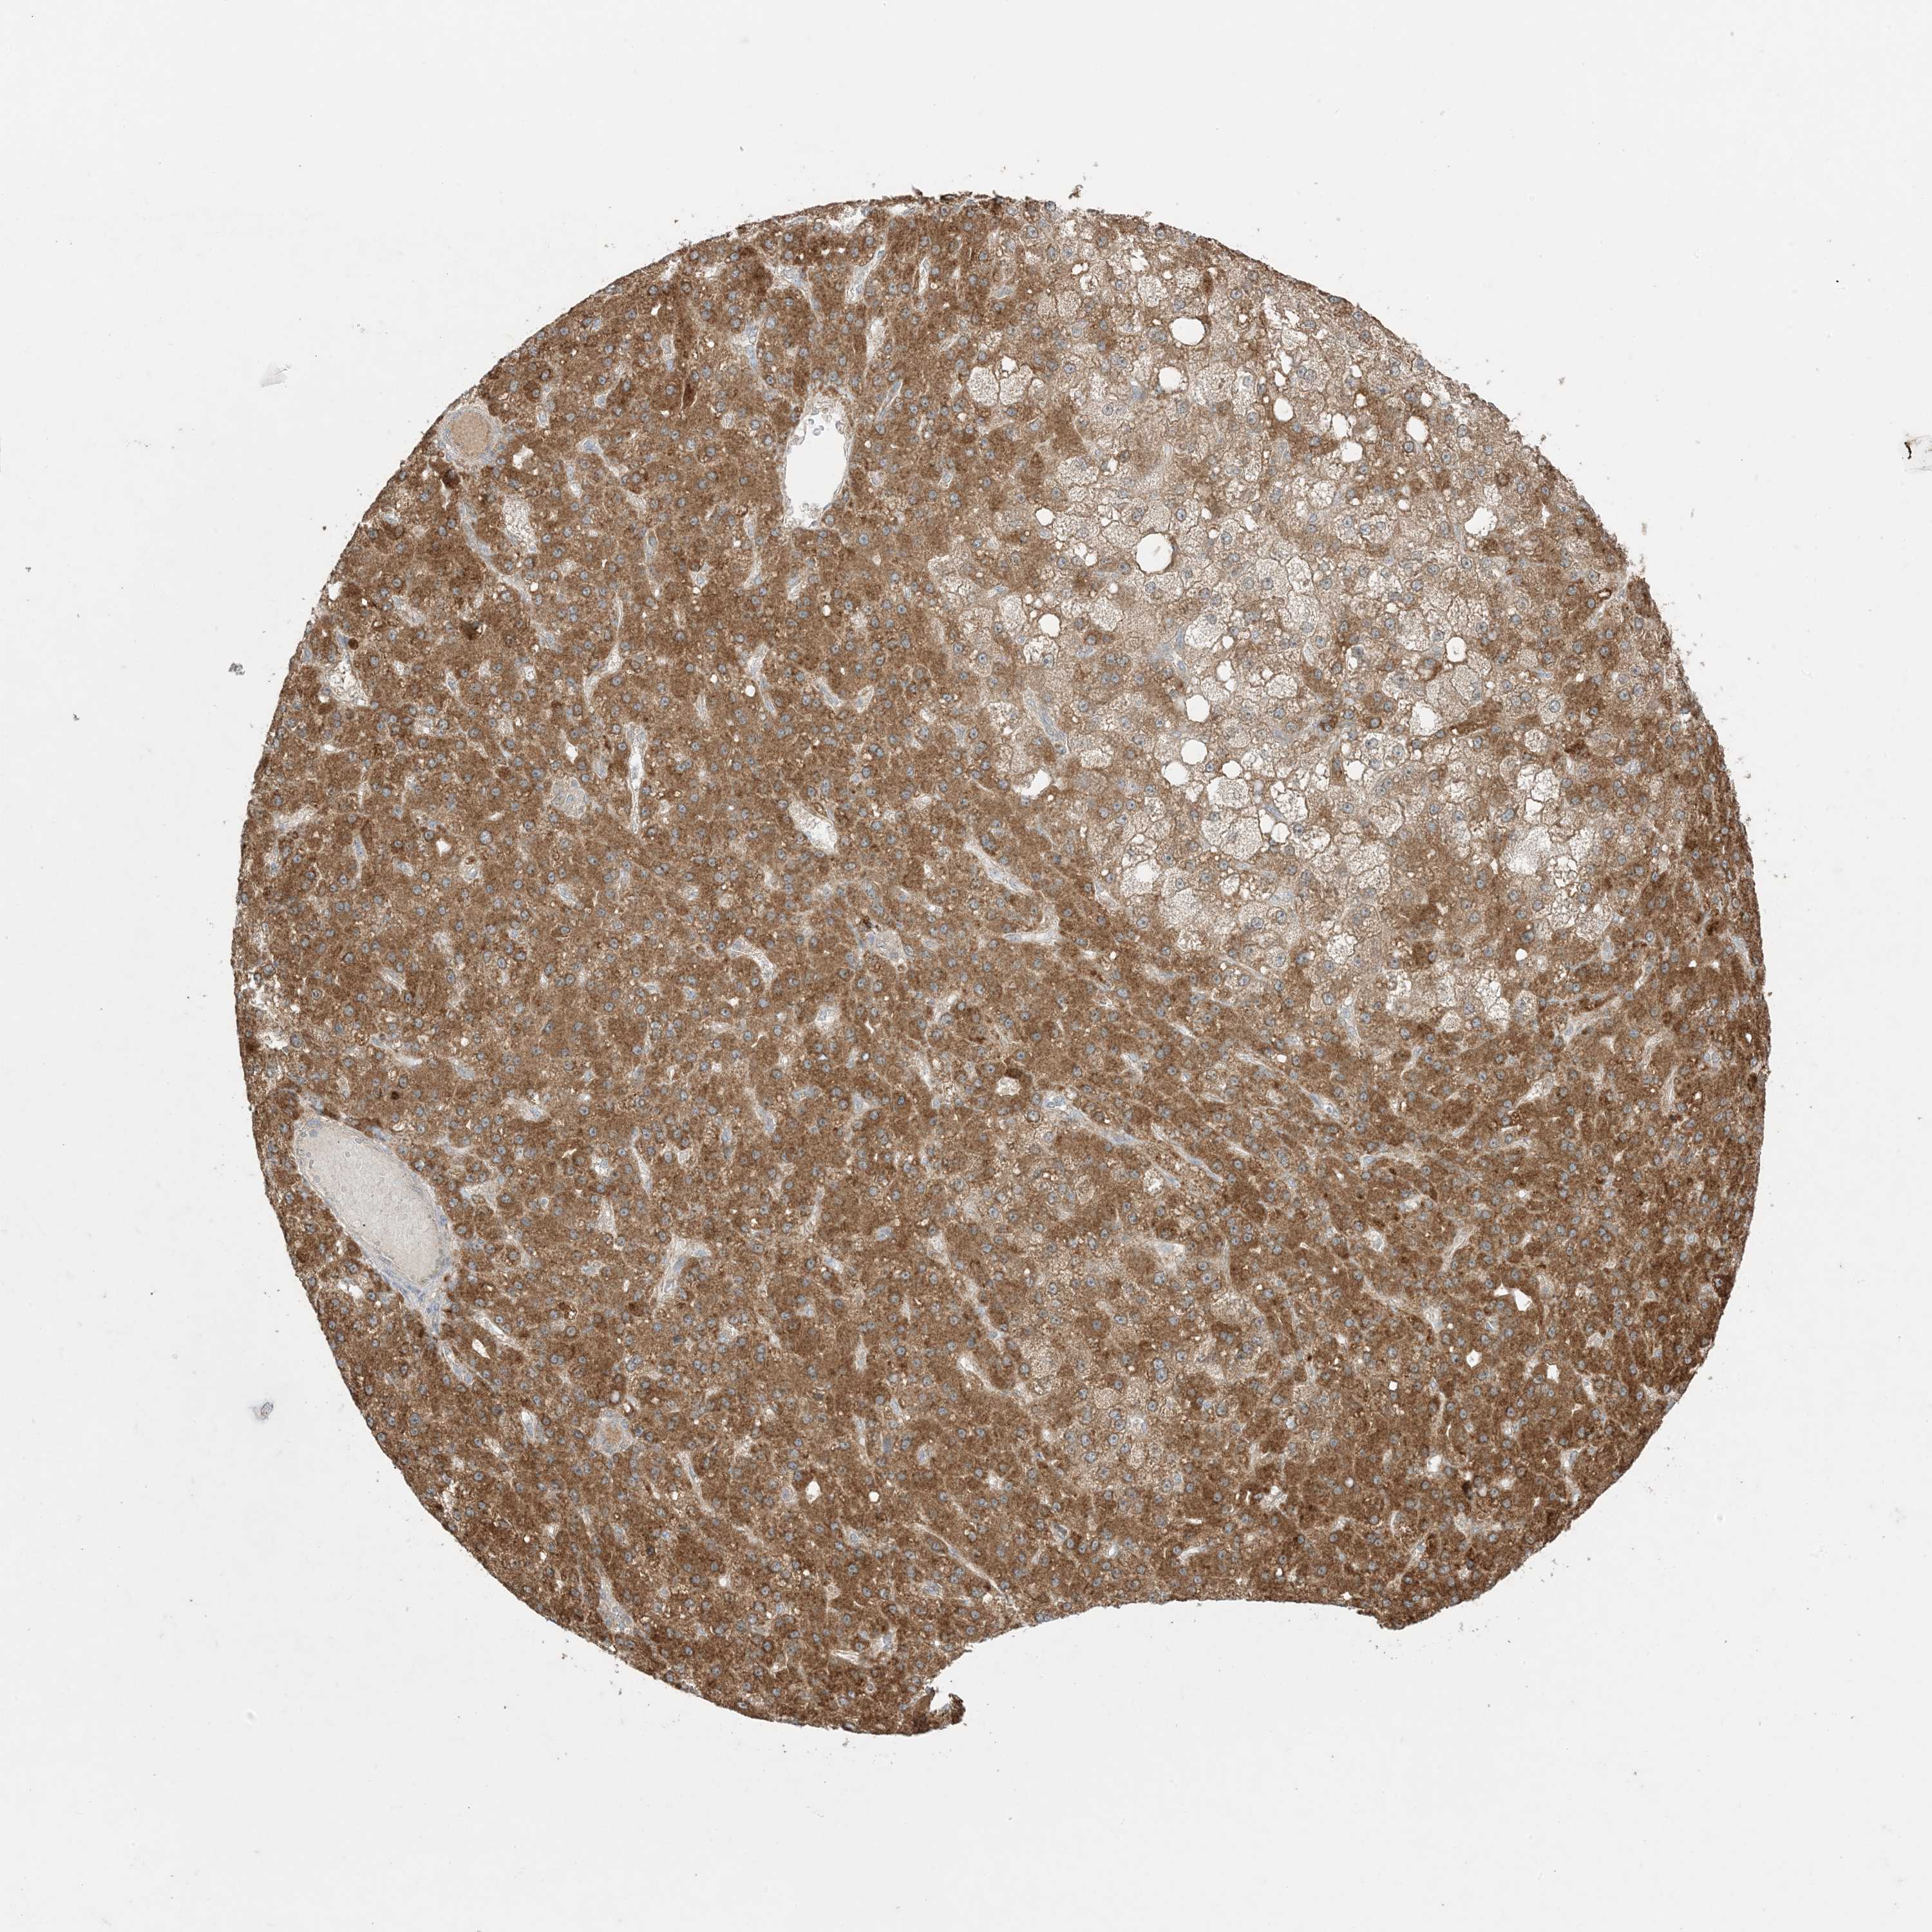

LIVER CANCER - Protein expressioni

A mouse-over function shows sample information and annotation data. Click on an image to view it in a full screen mode. Samples can be filtered based on level of antibody staining by selecting one or several of the following categories: high, medium, low and not detected. The assay and annotation is described here.

Note that samples used for immunohistochemistry by the Human Protein Atlas do not correspond to samples in the TCGA dataset.

Antibody stainingi

Antibody staining in the annotated cell types in the current human tissue is reported as not detected, low, medium, or high, based on conventional immunohistochemistry profiling in selected tissues. This score is based on the combination of the staining intensity and fraction of stained cells.

Each image is clickable and will lead to virtual microscopy that enables deeper exploration of all samples and also displays staining intensity scores, fraction scores and subcellular localization as well as patient and tissue information for each sample.

Antibody HPA001536

Antibody CAB035996

Staining

High

Medium

Low

Not detected

Intensity

Strong

Moderate

Weak

Negative

Quantity

>75%

75%-25%

<25%

None

Location

Nuclear

Cytoplasmic/membranous

Cytoplasmic/membranous,nuclear

Cholangiocarcinoma

Carcinoma, Hepatocellular, NOS